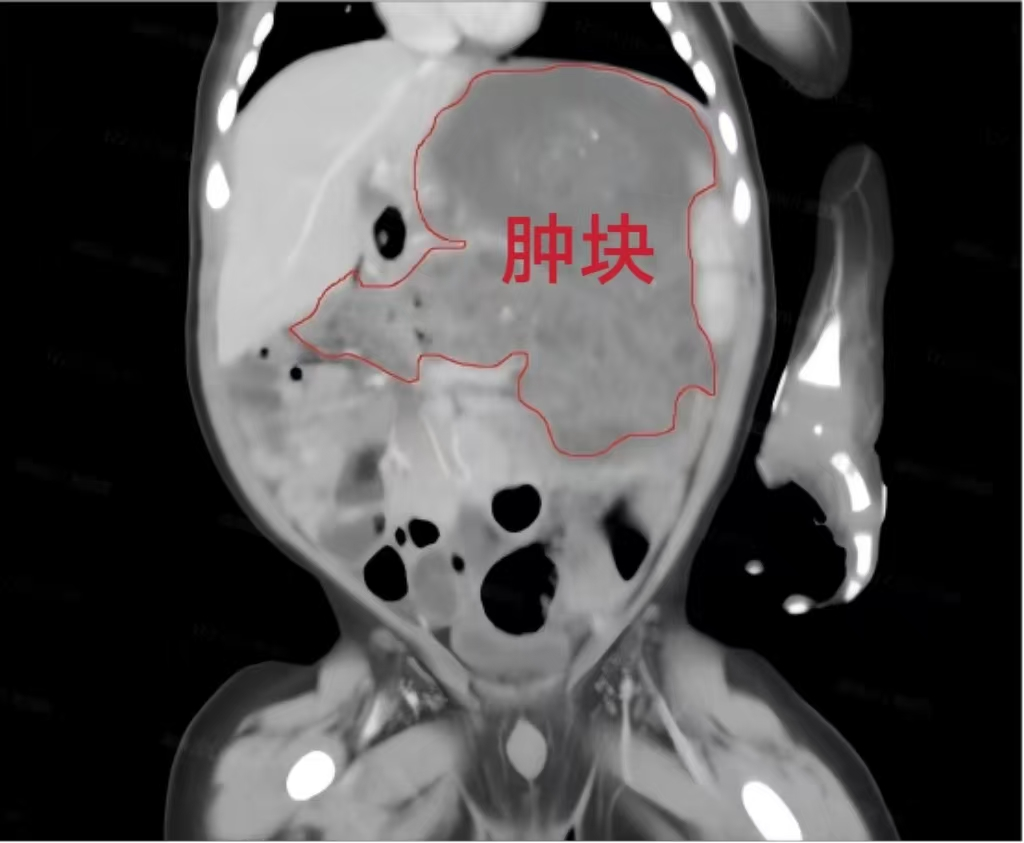

来自宁乡市的男婴小洋洋,因腹泻、排黑便在当地医院就诊治疗,腹部B超及腹部CT发现腹部有一肿块后转诊至我院。经进一步检查发现,洋洋整个左侧腹腔存在巨大占位病变,胃壁结构受侵,考虑为胃壁来源的畸胎瘤,且已压迫胃、肝脏及膈肌,并有持续增大趋势,存在破裂、出血、感染及恶变风险;同时因肿瘤压迫,洋洋吃奶缓慢、营养摄入不足,生长发育受到严重影响,手术成为唯一有效的治疗方式。

在周密的术前评估与准备后,胎儿与新生儿外科主任周崇高教授团队为洋洋实施胃部分切除术+胃壁修补术+腹腔肿瘤切除术。术中,团队精细分离肿瘤与周围组织,完整切除约10×8×7cm³的胃内肿瘤及胃外病灶,,肿块重400克,占据洋洋身体重量的十分之一。并妥善修补胃壁,最大限度地保护了洋洋消化道功能。手术过程顺利,洋洋生命体征平稳。